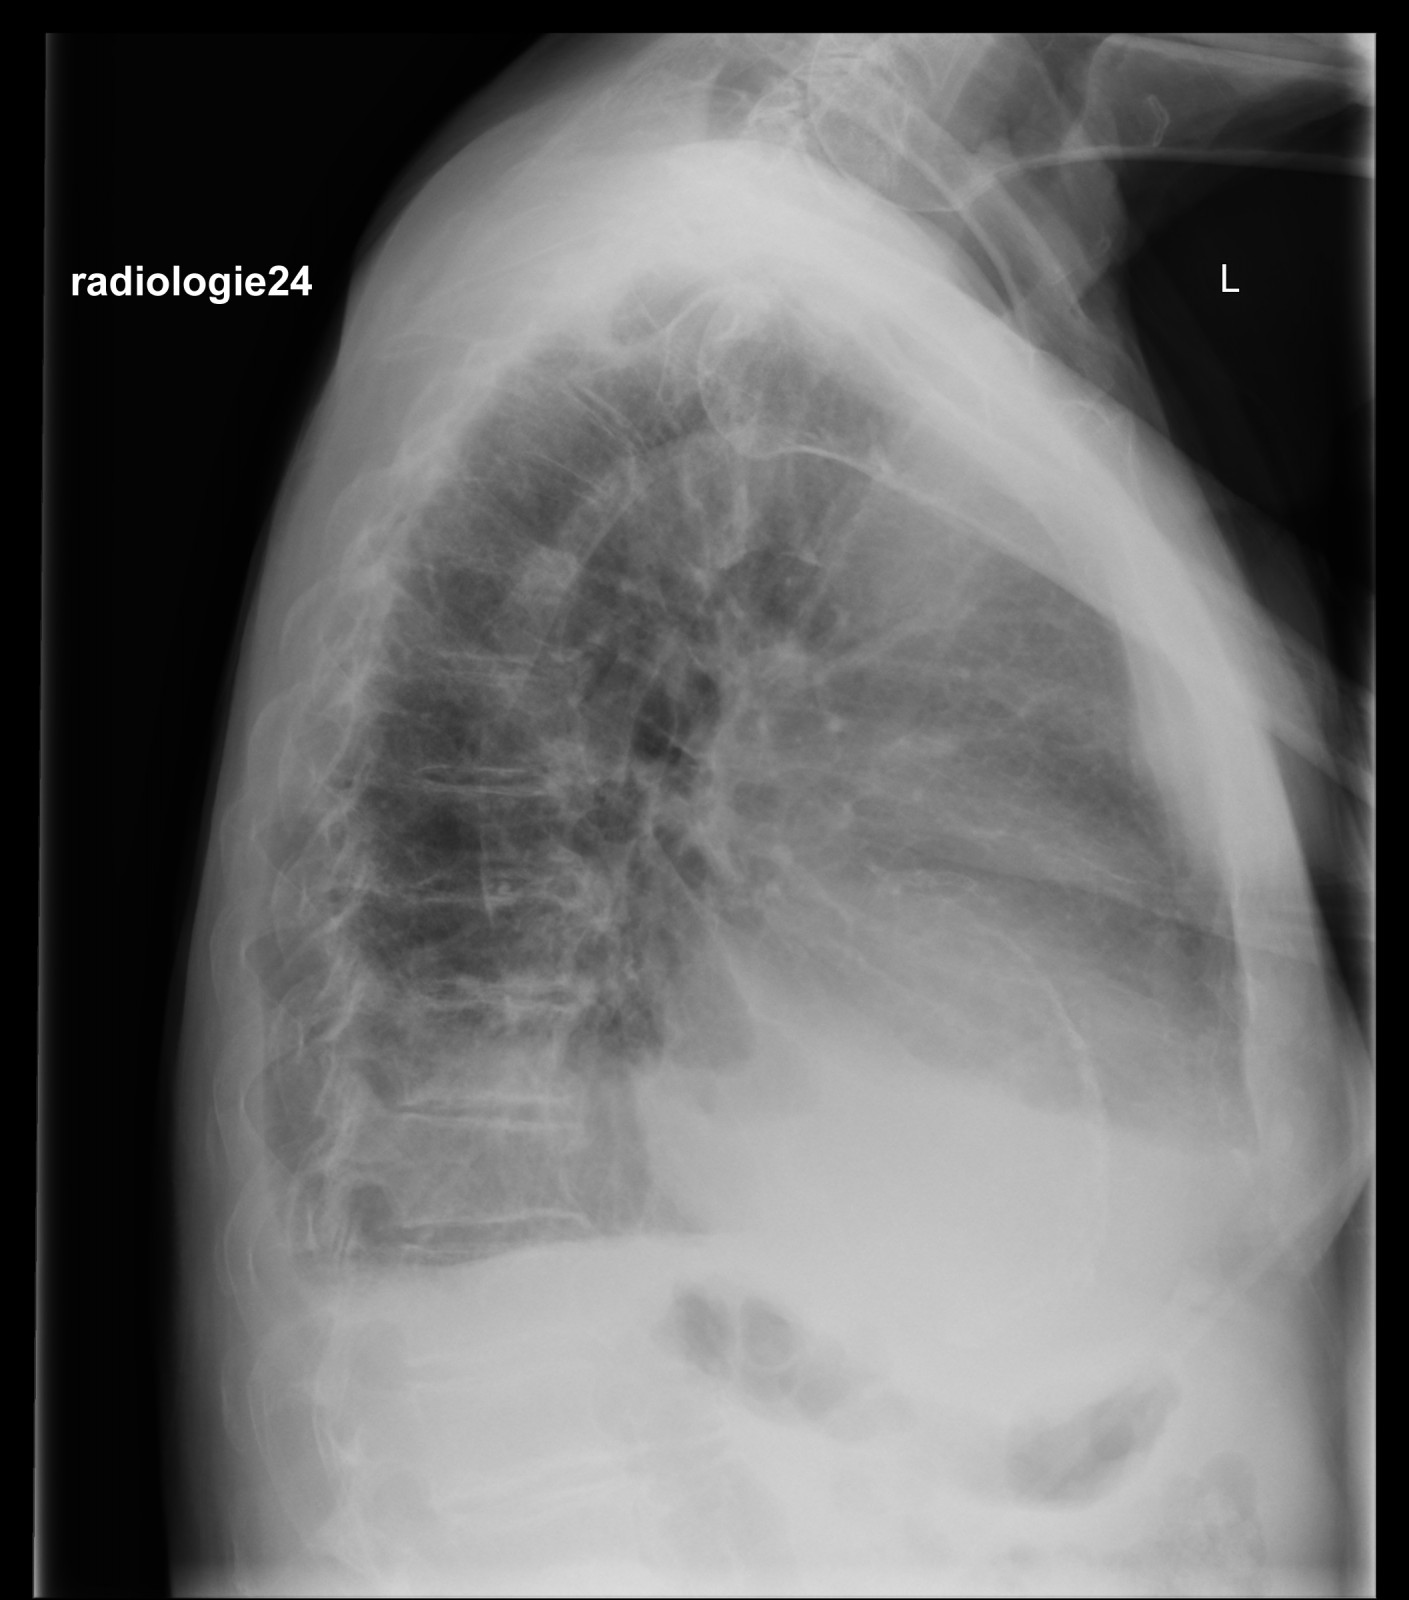

Röntgenfall des Monats Februar 2018 mit Auflösung

75 jähriger Patient Zunehmende Belastungsdyspnoe. Ihre Diagnose? Nebenbefunde?

Bild vergrössern